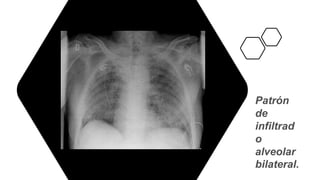

Imagen.

• Rx de tórax influenza que tengan:

• Exploración pulmonar anormal

• Sospecha de neumonía

Patrón

de

infiltrad

o

alveolar

bilateral.

Imagen. • Rx detórax influenza que tengan: • Exploración pulmonar anormal • Sospecha de neumonía • Tomografía de tórax: • Desaturación • Radiografía de tórax con datos sugestivos de neumonía • Algunos patrones tomográficos frecuentes en influenza son: • Vidrio despulido • Engrosamiento de pared bronquial • Localización difusa Prevención, diagnóstico y tratamiento de la Influenza estacional. Guía de Práctica Clínica: Guía de Referencia Rápida: México, CENETEC; 2020